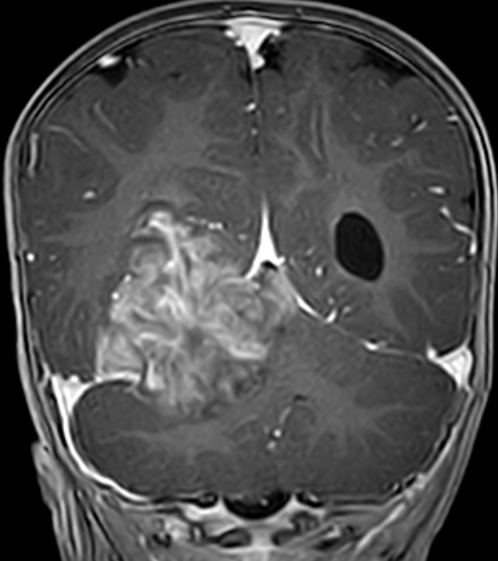

入院后,患儿头颅MRI平扫+增强提示:右侧小脑幕上下骑跨巨大肿瘤,压迫右侧丘脑、侧脑室、脑干、小脑等重要结构,考虑胚胎型肿瘤可能性大。肿瘤与周围组织无明显边界,手术难度极大、风险极高。

脑肿瘤术前1